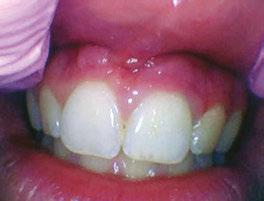

Several clinical solutions exist for primary anterior teeth with multisurface decay. Full coronal restoration of carious primary incisors may be indicated when caries is present on multiple surfaces, pulpal therapy is indicated, caries may be minor, but oral hygiene is very poor, or in a child with severe early childhood caries or a high caries risk diagnosis.1 Depending on the clinical scenario, a minimally invasive approach with the utilization of a high viscosity glass ionomer cement (HVGIC), with or without the combination of silver diamine fluoride (SDF) in a strip crown form, may pause the caries progression and provide an adequate clinical solution. Resin composite strip crowns have shown 80% retention rates and adequate parental satisfaction,1-4 although composite resin strip crowns have shown lower retention rates in teeth with decay involving three or more surfaces and particularly in children with a high caries risk4-6 (Figure 1). This could be from the continued high caries risk behaviors of the patient, as composite resin strip crowns in this population have shown to have increased inflamed marginal gingiva and gingival bleeding, increased plaque retention along the restoration, and loss of some restorative material.5,6

2: NuSmile® Anterior Zirconia crowns at 2-year follow up. Note the high amount of plaque accumulations along the untreated cuspid and existing stainless-steel crowns

A 2-year-old male who received full mouth dental rehabilitation (FMDR) under general anesthesia presented for his 6-month recall at 2-year post FMDR. He had significant plaque accumulations with poor oral hygiene along his existing stainless-steel crowns (SSCs) and non-treated teeth. Additionally, the patient had gingival bleeding and gingival inflammation

Figure 1: Occlusal films at recall visit in high caries risk patients showing loss of material and recurrent decay in composite resin strip crowns Figure

around these clinical sites. His anterior zirconia crowns showed healthy gingival margins with little-to-no plaque accumulations. This positive clinical finding is from the highly polished nature and biocompatibility of pediatric zirconia crowns. These restoration features limit plaque accumulations on the restoration and along the marginal gingiva, providing a localized positive aspect directly related to the choice of restorative material (Figure 2).